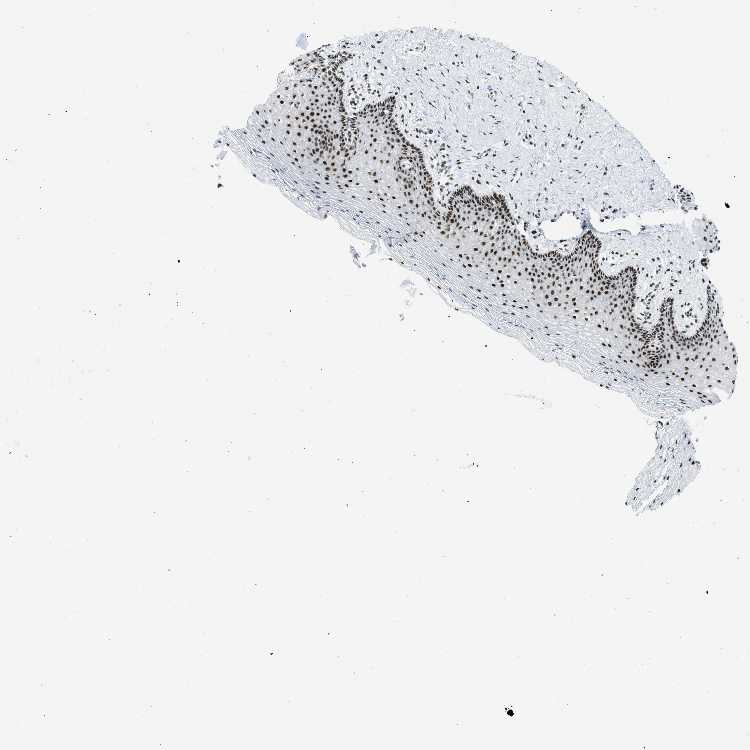

VAGINA - Antibody stainingi

Antibody staining in the annotated cell types in the current human tissue is reported as not detected, low, medium, or high, based on conventional immunohistochemistry profiling in selected tissues. This score is based on the combination of the staining intensity and fraction of stained cells.

Each image is clickable and will lead to virtual microscopy that enables deeper exploration of all samples and also displays staining intensity scores, fraction scores and subcellular localization as well as patient and tissue information for each sample.

Antibody HPA018334

Squamous epithelial cells High